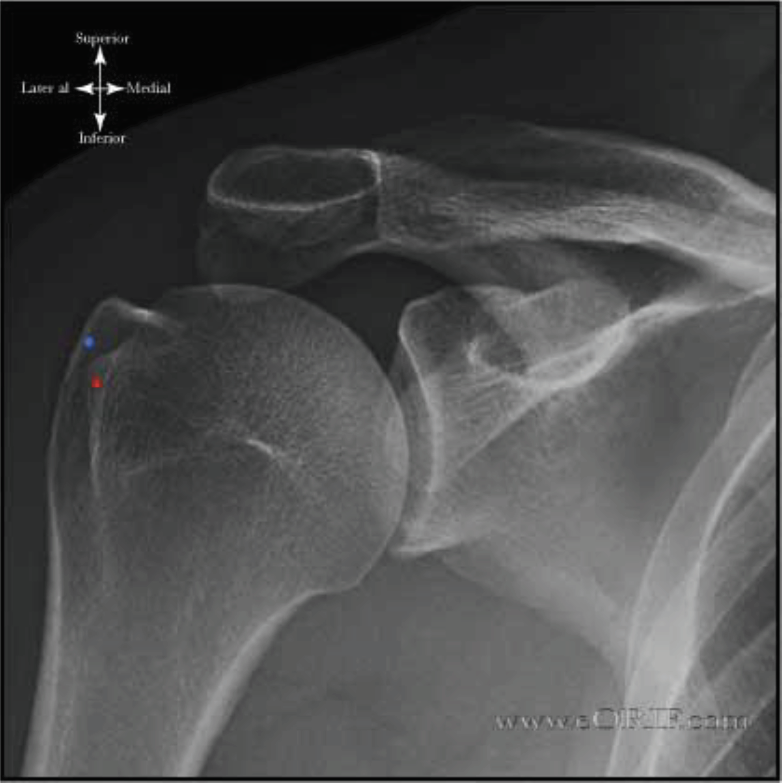

What is this view of the shoulder? what views are missing?

AP internal rotation

MISSING:

AP

AP external rotation

Axial

Scapular Y Shoulder

AC Joints (spot, weighted